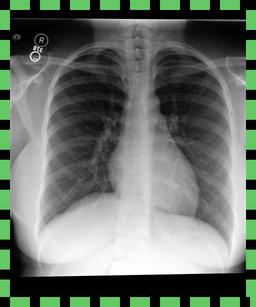

We found that many lateral acquisitions in the dataset were unexpectedly labelled as frontal (Figure 7(a)). Some images contained only noise (Figure 7(b)), non-human samples (Figures 7(d) and 7(e)) or incorrect anatomy (Figure 7(g)). Often, acquisitions with an incomplete field of view (FOV) (i.e., the lungs are not completely visible) were repeated (Figure 7(c)). Lastly, post-processed images were detected by the algorithm such as contrast-enhanced scans (Figure 7(i)) that are not often used for diagnostic purposes in clinical practice.

Curation of imaging datasets

CXR datasets [36] often contain multiple image acquisitions in a single visit due to data quality issues such as a limited field-of-view or scanning the wrong body part (Figure A.7). Unlike [9, 32, 81], we conduct curation to choose higher quality images among the potential candidates instead of performing a random selection. For this step, a separate BioViL-T is trained on ‘clean’ studies with single acquisitions and later used in a zero-shot setting to detect out-of-distribution samples [26, 27] arising from the re-imaging process. The candidate is selected as follows: for a margin . This approach is applied to enhance the quality of the temporal classification dataset given its limited size.